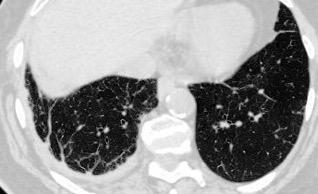

< 80% hallazgos pulmonares. Colección con calcificaciones. Micronódulos en intersticio subpleural y broncovascular con engrosamiento septal. Respuesta paradójica frecuente.

Shaw JA et al. Tuberculous pleural effusion. Respirology 2019.

Pleura engrosada > 2 mm

Rx. 50%

TC. 60%

Engrosamiento > 10 mm

20-46%

Fibrotórax difuso uniforme 5-55%.